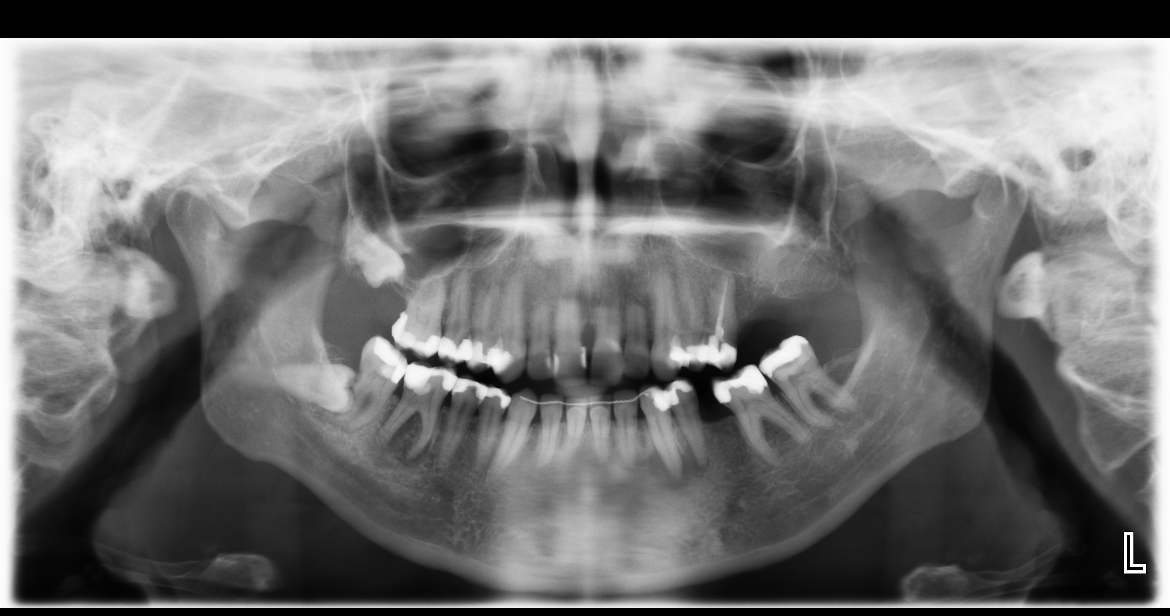

Wie kan mij helpen. Na lang uitstellen heb ik toch maar een afspraak gemaakt bij de kaakchirurg ingepland om mijn verstandskies eruit te halen die dwars ligt. (23 februari) De kiest daarnaast blijft staan en in de andere kies die daar naast staat zou een ontsteking zitten in de wortelpunt. Ik schrok heel erg van de kosten dus twijfel nu wat te doen. Of een wortelkanaalbehandeling of door de vele vullingen die al in deze tand zitten deze ook maar te trekken. Ik ben erg onzeker over mijn gebit door alle vullingen die ik heb in met name de kiezen. Aan de andere kant van mijn gebit is namelijk ook al een kies getrokken omdat deze gewoon heel zwak was en constant afbrak.

Ik hoop dat ik nog wel even met mijn tanden kan doen. Wat vind je op dit moment van de foto?

Zie je een grote ontsteking? Of kan dit nog behandeld worden met een antibiotica kuur.

Verstand kies verwijderen, wkb 46 ( eerste grote kies flinke ontsteking niet met AB kuur goed te krijgen) later kroon ( als u kiest voor behoud met vaste voorzieningen).....